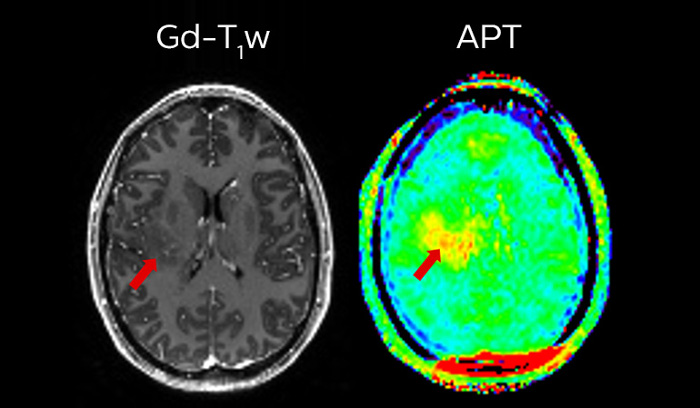

APT** and REACT**: The next steps towards non-invasive imaging strategies for pediatric MRI